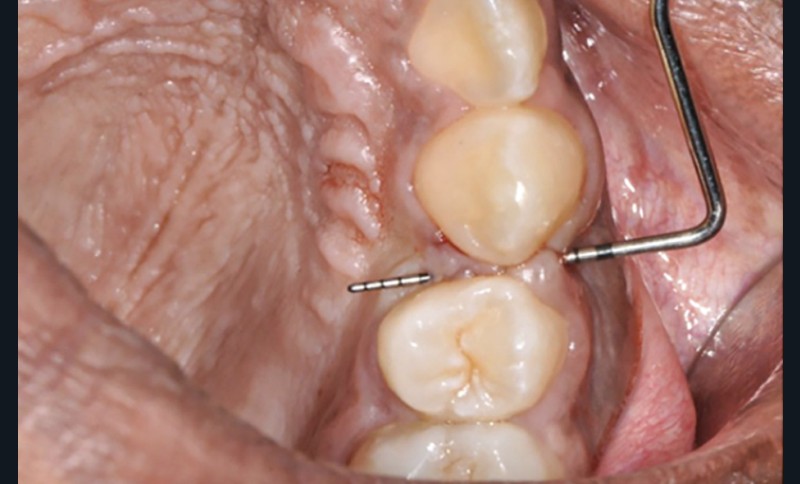

Au total, 23 patients ayant achevé leur traitement orthodontique au moins 3 mois auparavant ont été recrutés au sein de la structure interne d’Orthopédie Dento-Faciale des Hôpitaux Universitaires de Strasbourg. Nous avons étudié les caractéristiques de 70 sites d’avulsions au total. La présence ou l’absence de fente ainsi que les caractéristiques parodontales de chaque site ont été relevées (biotype gingival, indice de plaque, indice de saignement au sondage, hauteur de gencive attachée). La sévérité des fentes a été caractérisée à l’aide de l’indice de Reichert [6]. Des données concernant le déroulement et la durée du traitement orthodontique ont été recueillies rétrospectivement dans les dossiers des patients. Ces mêmes paramètres ont également été testés afin d’évaluer une possible association avec la sévérité de la fente (fig. 2).